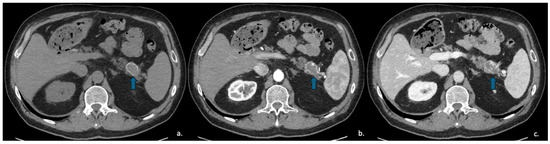

Pancreatic Cystic Lesions: From Basic Knowledge to Recent Guidelines

by Ginevra Danti, Ludovica Scalzone, Lavinia Mattolini, Matilde Anichini, Francesca Treballi, Linda Calistri, Diletta Cozzi and Vittorio Miele

Pancreatic cystic lesions (PCLs) are increasingly detected due to widespread use of cross-sectional imaging. They encompass a heterogeneous group of lesions, ranging from benign pseudocysts and serous cystic neoplasms (SCNs) to premalignant mucinous cystic neoplasms (MCNs) and intraductal papillary mucinous neoplasms (IPMNs), as [...] Read more.

Pancreatic cystic lesions (PCLs) are increasingly detected due to widespread use of cross-sectional imaging. They encompass a heterogeneous group of lesions, ranging from benign pseudocysts and serous cystic neoplasms (SCNs) to premalignant mucinous cystic neoplasms (MCNs) and intraductal papillary mucinous neoplasms (IPMNs), as well as rare malignant entities such as solid pseudopapillary epithelial neoplasm (SPENs) and cystic pancreatic neuroendocrine tumors (cystic PanNETs). Management of PCLs depends on their malignant potential; therefore, an accurate classification is essential for optimizing treatment. This narrative review summarizes current knowledge on the epidemiology, imaging characteristics, diagnosis, and management of PCLs, highlighting the role of CT, MRI, MRCP, and endoscopic ultrasound. Recent advances in radiomics for lesion characterization and risk stratification, particularly in IPMNs, are discussed. Full article

Show Figures

Figure 1